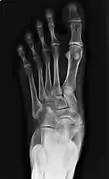

Radiological images